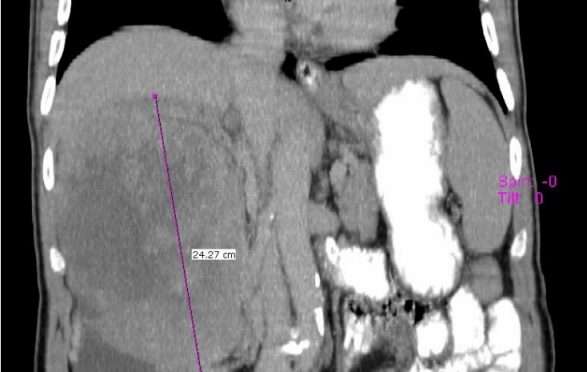

Është dashur më shumë se 6 orë e 30 minuta operacion që pacientit I.SH, i lindur më 1954, t’i hiqet një tumor masiv në veshkën e djathtë, transmeton albinfo.ch.

“Tumori ishte me madhësi gjigante, duke filluar nga kraharori e deri në pjesën e poshtme të abdomenit ( stomakut ), duke mbuluar në tërësi enët e mëdha të gjakut ( Vena kava inderior) dhe duke hyrë në thellësi në anën e pasme të mëlçisë. Ndërhyrja kirurgjikale ishte mjaftë sfiduese, me mundësi të lëndimit të enëve të mëdha të gjakut (siç është vena cava inferior të cilën tumori e kishte mbuluar në tërësi në gjatësi prej 18 cm ) dhe mëlçinë”, njofton zyra për media e QKUK-së.

Aty theksohet se operacioni ka shkuar mirë, duke e hequr në tërësi tumorin, pa pasur asnjë komplikim dhe gjendja e pacientit është stabile.

Në përvojën e ekipit mbi 30 vjeçare, nuk është realizuar ndonjëherë një ndërhyrje e tillë kirurgjikale.